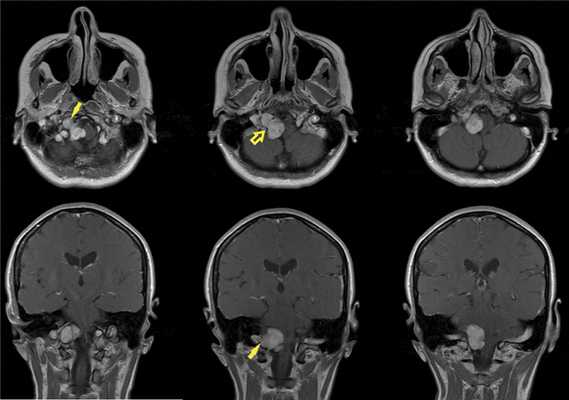

По данным МРТ головного мозга с усилением сигнала парамагнетиком выявлена опухоль парастволовой локализации справа, компримирующая продолговатый мозг и исходящая из расширенного канала подъязычного нерва. Меньший по размерам компонент опухоли располагался в полости канала и распространялся экстракраниально (рис. 1). Рис. 1. МРТ головного мозга пациентки В. до операции. При усилении сигнала выявляется опухоль справа, соответствующая невриноме, в форме «гантели», располагающаяся одной частью на уровне краниовертебрального перехода и вызывающая компрессию ствола мозга, а другой — частью в костных структурах.

При СКТ головного мозга в костном режиме выявлен расширенный канал подъязычного нерва с деструкцией его стенок. Заднелатеральная стенка практически отсутствовала, вследствие чего полость канала сообщалась с просветом яремного отверстия (рис. 2). Рис. 2. СКТ головного мозга пациентки В. в костном режиме до операции. Определяется деструкция канала подъязычного нерва справа, канал отделен от полости яремного отверстия тонкой костной перегородкой (указано стрелкой).

При проведении диффузионно-тензорной трактографии реконструированы каудальная группа нервов и кортикоспинальный тракт. Последний компримирован опухолью и оттеснен влево. На нижнем полюсе располагались корешки верхних шейных сегментов спинного мозга и подъязычного нерва. Языкоглоточный и блуждающий нерв располагались на верхнем полюсе опухоли и были деформированы (рис. 3). Рис. 3. Диффузионно-тензорная трактография головного мозга пациентки В. до операции. Определен кортикоспинальный тракт в стволе головного мозга, на верхнем полюсе опухоли располагаются языкоглоточный и блуждающий нервы, по переднему полюсу проходят добавочный нерв и корешок СI. а — кортикоспинальный тракт, б — корешки IX, X, XI черепно-мозговых нервов, в — акустико-фациальная группа нервов, г — опухоль.

При проведении МРТ головного мозга пациентки В. на 3-и сутки после операции выявлена остаточная часть опухоли в канале подъязычного нерва (рис. 5). Рис. 5. МРТ головного мозга пациентки В. на 3-и сутки после операции. При усилении сигнала парамагнетиком определяется остаток опухоли в канале подъязычного нерва справа (указано стрелкой).